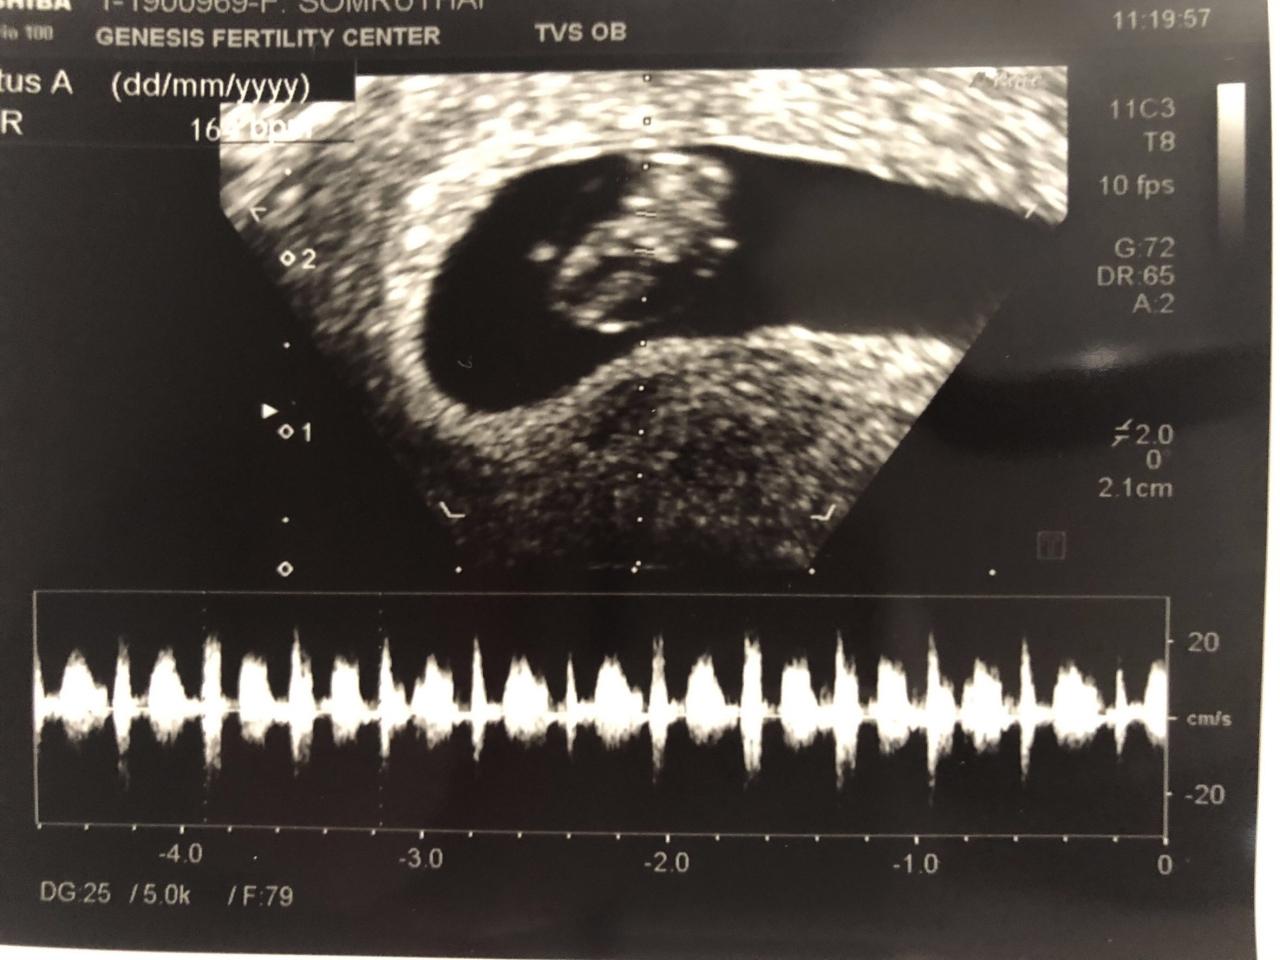

ยิ้มไม่หุบมีความสุขที่สุดหลังจากได้เห็นภาพลูกครั้งแรก สำหรับว่าที่คุณพ่อ ต๊ะ บอยสเก๊าท์ หรือ วินรวีร์ ใหญ่เสมอ ที่ล่าสุดได้ลงคลิป VDO ในอินสตาแกรมของตัวเอง ระหว่างที่พาภรรยาคนสวย บุ๋ม มินตยา ไปอัลตราซาวนด์

เมื่อว่าที่คุณพ่อต๊ะได้เห็นภาพของลูก เจ้าตัวก็เก็บอาการของความสุขไว้ไม่อยู่ยิ้มไปถ่ายคลิปไปตลอดเวลา พร้อมบอกลูกคือสิ่งที่วิเศษที่สุดในชีวิตตัวเองจริงๆ โดยหนุ่มต๊ะ บอยสเก๊าท์ บอกว่า